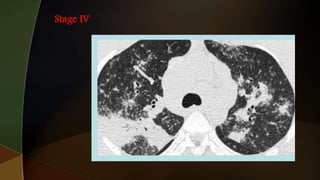

1. hilar adenopathy alone

2. hilar adenopathy plus infiltrates;

3. infiltrates alone;

4. fibrosis

1. hilar adenopathyalone 2. hilar adenopathy plus infiltrates; 3. infiltrates alone; 4. fibrosis